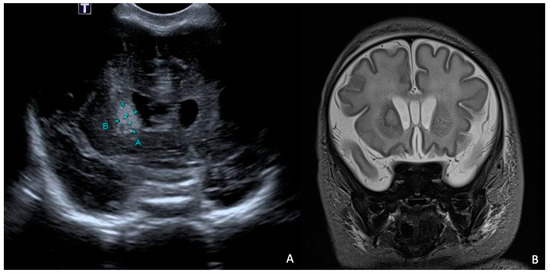

Rapid molecular tests on CSF (later confirmed by CSF and blood cultures) revealed a pan-sensitive E. coli K1. Ampicillin and gentamicin were discontinued and replaced by fosfomycin, continuing with cefotaxime. At eight days of life, a brain MRI was performed, showing a collection in the left frontal subdural site with a maximum thickness of approximately 7 mm and multiple subcentimetric subtentorial and supratentorial collections compatible with empyema; the collection in the left parietal site was subsequently evaluated by ultrasound until resolution (Figure 4). Therapy was prolonged for a total of 24 days (22 with fosfomycin), with no adverse events reported.

Figure 4. (A), Brain MRI in FLAIR sequence with evidence of left parietal subdural collection and multiple diffuse supra- and infratentorial subcentimetric collections. (B,C) HUS: left parietal subdural collection, with maximum thickness of 7 mm.